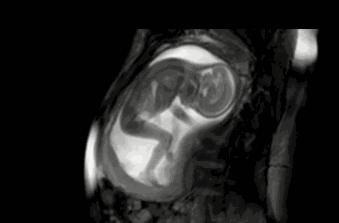

在胎宝宝的胸腔和腹腔之间,有膈肌将它们隔开。膈肌有神经分布和血液供应,当引起打嗝的诱因刺激传导给大脑之后,大脑就会发出指令,让膈肌出现一阵阵的收缩,于是就打嗝了。

△B超下正在打嗝的胎宝宝

至于是什么刺激了膈肌目前还不清楚, 不过有的研究认为和胎宝宝在妈妈体内不断吞咽羊水,锻炼肺部呼吸能力有关 。